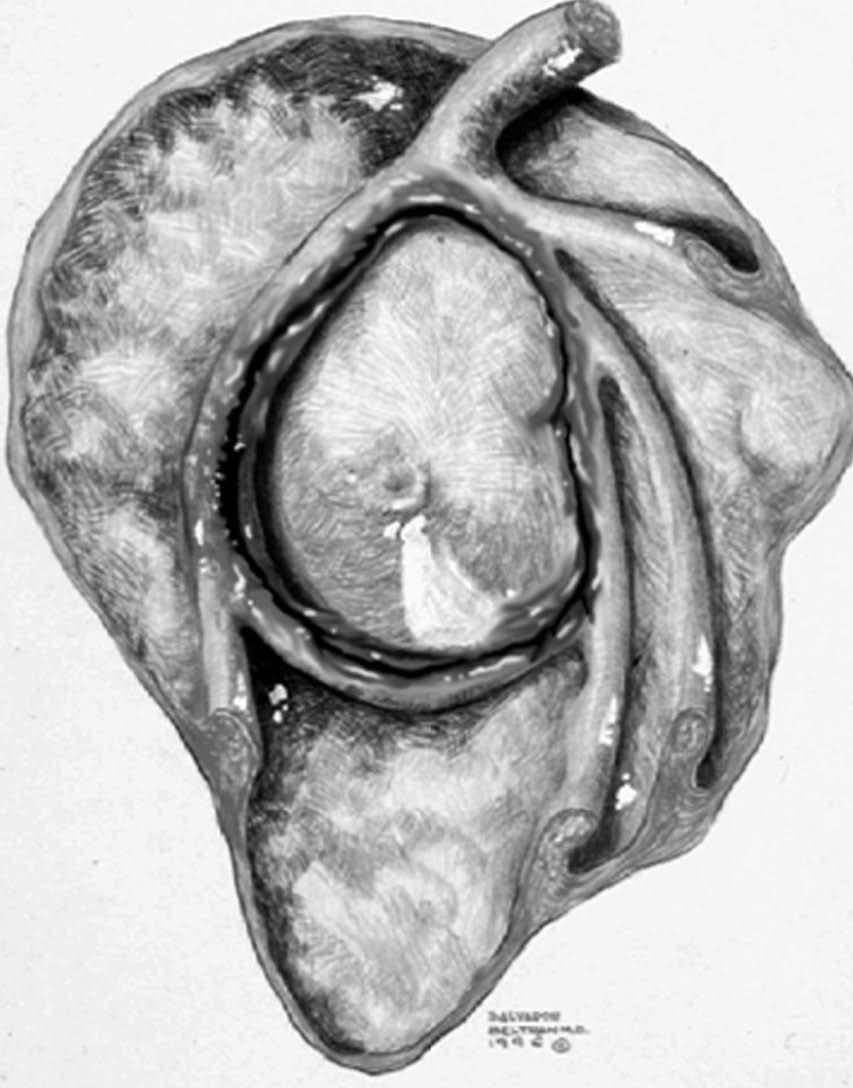

ALPSA (anterior labroliamentous periosteal avulsion)

Al igual que en el apartado anterior, existe también una separación de LG junto con la cápsula y el periostio, pero a diferencia de las lesiones de Bankart o Perthes, el LG se desplaza hacia dentro, por detrás del borde de la glenoides18 (fig. 12). La lesión de ALPSA puede cicatrizar por sinovialización (fig. 12), pero continúa siendo de carácter inestable.

Fig. 12.--ALPSA (anterior labroliamentous periosteal avulsion) agudo (A) y crónico (B). Nótese la separación del labio glenoideo y su desplazamiento posterior y medial por detrás del reborde glenoideo (flecha en A). En una fase crónica el labio glenoideo no se distingue como una estructura separada, sino como un engrosamiento de la unión entre el labio, la cápsula y el periostio (flecha en B).